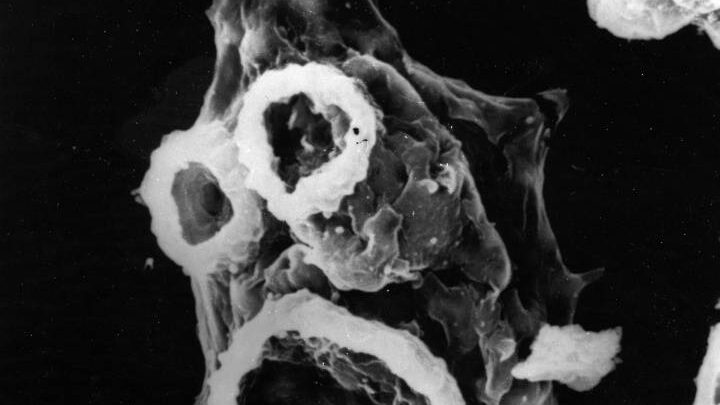

De acuerdo a lo que informa Infobae, el comunicado no detalló la identidad del paciente ni la posible forma en la que se habría infectado con la Naegleria Fowleri, un organismo microscópico unicelular que puede causar meningoencefalitis amebiana primaria, una rara enfermedad que destruye el tejido cerebral con un mínimo porcentaje de supervivencia.